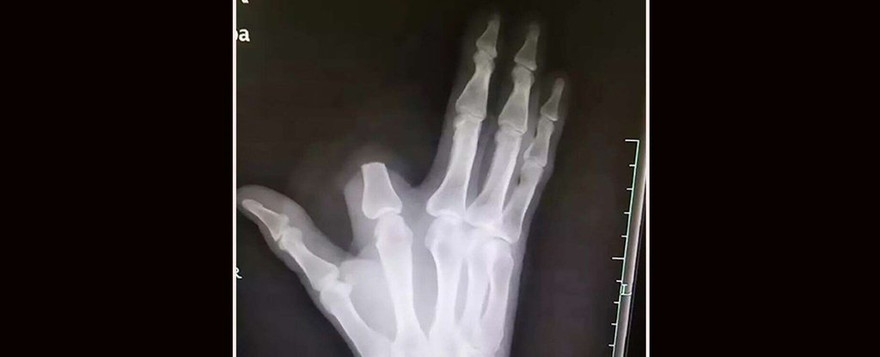

TPO - Sau khi bị rắn độc cắn, người nông dân Trung Quốc đã chặt ngón tay vừa bị cắn của mình với hy vọng giảm thiểu nọc độc giúp ông có thời gian đi đến bệnh viện gần nhất.

Sau đó, để ngăn nọc độc lây lan, người đàn ông 60 tuổi đã nhanh chóng tự cắt bỏ vị trí bị rắn cắn. Ông ta quấn vết thương bằng vải và thực hiện chuyến đi dài 80 km (50 dặm) đến một bệnh viện ở Hàng Châu để được điều trị.

Vị bác sĩ điều trị cho người đàn ông bị rắn cắn đã xác nhận rằng bệnh nhân hiện đang ổn định, không có dấu hiệu chảy máu, đau đầu, chóng mặt. Bác sĩ còn nhấn mạnh rằng, hành động tự chặt ngón tay của người đàn ông kia là hoàn toàn không cần thiết. Việc xử trí vết thương rắn cắn theo cách này là lỗi thời, bác sĩ nói thêm, nó không mang lại lợi ích nào cả .